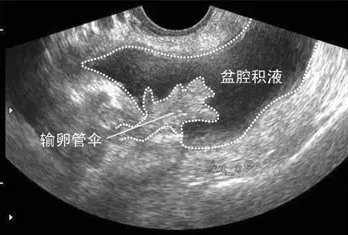

盆腔积液大多是盆腔存在炎性渗出物,常表现为小腹下坠、胀痛,腰酸腰痛、月经紊乱、不孕等,那具体盆腔积液是怎么引起的呢?盆腔积液是怎么回事?盆腔积液的危害有哪些?盆腔积液的产生主要可分为生理性因素和病理性因素两种。

生理性盆腔积液是指正常的盆腔积液,不需要治疗。人体的盆腔、腹腔并不是干巴巴的一块「土地」,腹膜、大网膜、肠管等都会分泌一些液体,这些液体通常起到润滑和保护盆腹腔器官和组织的作用。盆腔积液可通过 B 超检查观察到,如果积液的深度小于 3 cm,没有其他不舒服的症状,通常是不需要处理的。

不孕是盆腔积液最常见的症状。如果盆腔炎导致输卵管堵塞,就会出现不孕。